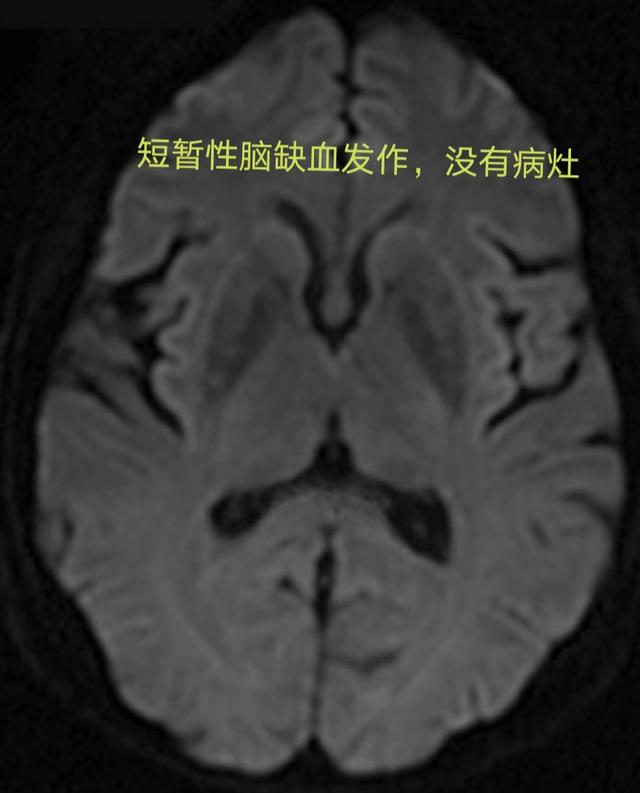

脳梗塞が起こる前の最も重要なシグナルの一つがTIAと呼ばれるもので、中国語では一過性脳虚血発作と訳される。これはどういうことかというと、脳の血管が突然けいれんを起こして収縮し、その結果、脳への酸素や栄養の供給が減少して、脳梗塞と同じような症状を引き起こすというものである。ただし、このとき血管が詰まっているわけではなく、痙攣して狭くなっているだけで、数分から数時間後には自然に元に戻り(時間は通常1時間以内)、症状は消失する。もしTIAが起これば、その人の脳血管に問題があり、将来脳梗塞を起こす可能性が非常に高いことを示唆している。この時、患者は急いで病院に行き、検査と予防をしなければならない。

一過性脳虚血発作(TIA)脳、脊髄、網膜の一部に血液が流れているように見える。短期閉塞これは、次のことにつながる可能性がある。一過性脳梗塞の症状,症状は軽く、通常は数分しか続かない。すぐに血管は自力で再開通した。脳組織の損傷や後遺障害はない。

一過性脳虚血発作患者の症状の持続期間は長くないので,受診時には正常と思われる患者がほとんどであるが,頭部CTや磁気共鳴画像などの検査も改善する必要がある。 画像検査で脳梗塞病変が見つからなければ一過性脳虚血発作と診断し,同時に同様の症状を呈する脳出血も除外することができる。この時点では、症状は軽快しているが、それ以上の診断や治療が必要ないわけではなく、頭頸部の血管病変の重症度を明らかにするために、頭部CT血管造影、磁気共鳴血管造影、血管造影などを改善し、妥当な治療計画を立てる必要がある。重要なのは脳梗塞の初期にはCTやMRIでは脳梗塞巣は検出できず、一過性脳虚血発作の持続時間は最大でも24時間であり、この24時間の間に一過性脳虚血発作と脳梗塞をどのように鑑別するか?初期の脳梗塞巣を検出できる拡散強調MRIで鑑別できる。